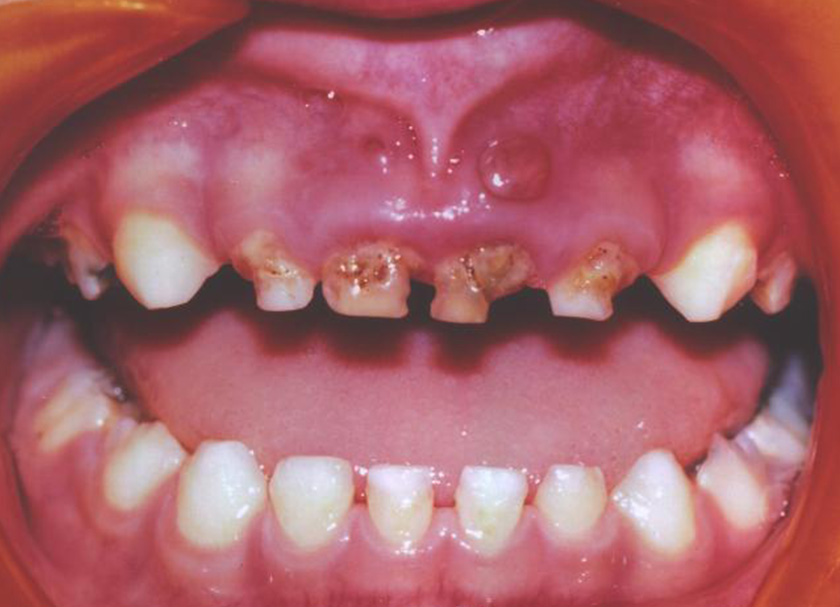

Nursing Bottle Caries

Nursing bottle caries or cavities are formed on the baby’s tooth and lead to decay, damaging the teeth. Often kids are seen holding a pacifier or nursing bottle for a longer duration for having sugary drinks or juices leads to cavity formation and tooth decay.

Different children experience different symptoms of nursing caries. Some common symptoms observed are white spots on the teeth, discoloring of teeth to brown color, fever caused by gum infection, and some experience pain and swelling too.

The upper incisors and molar teeth are severely affected by the nursing bottle.